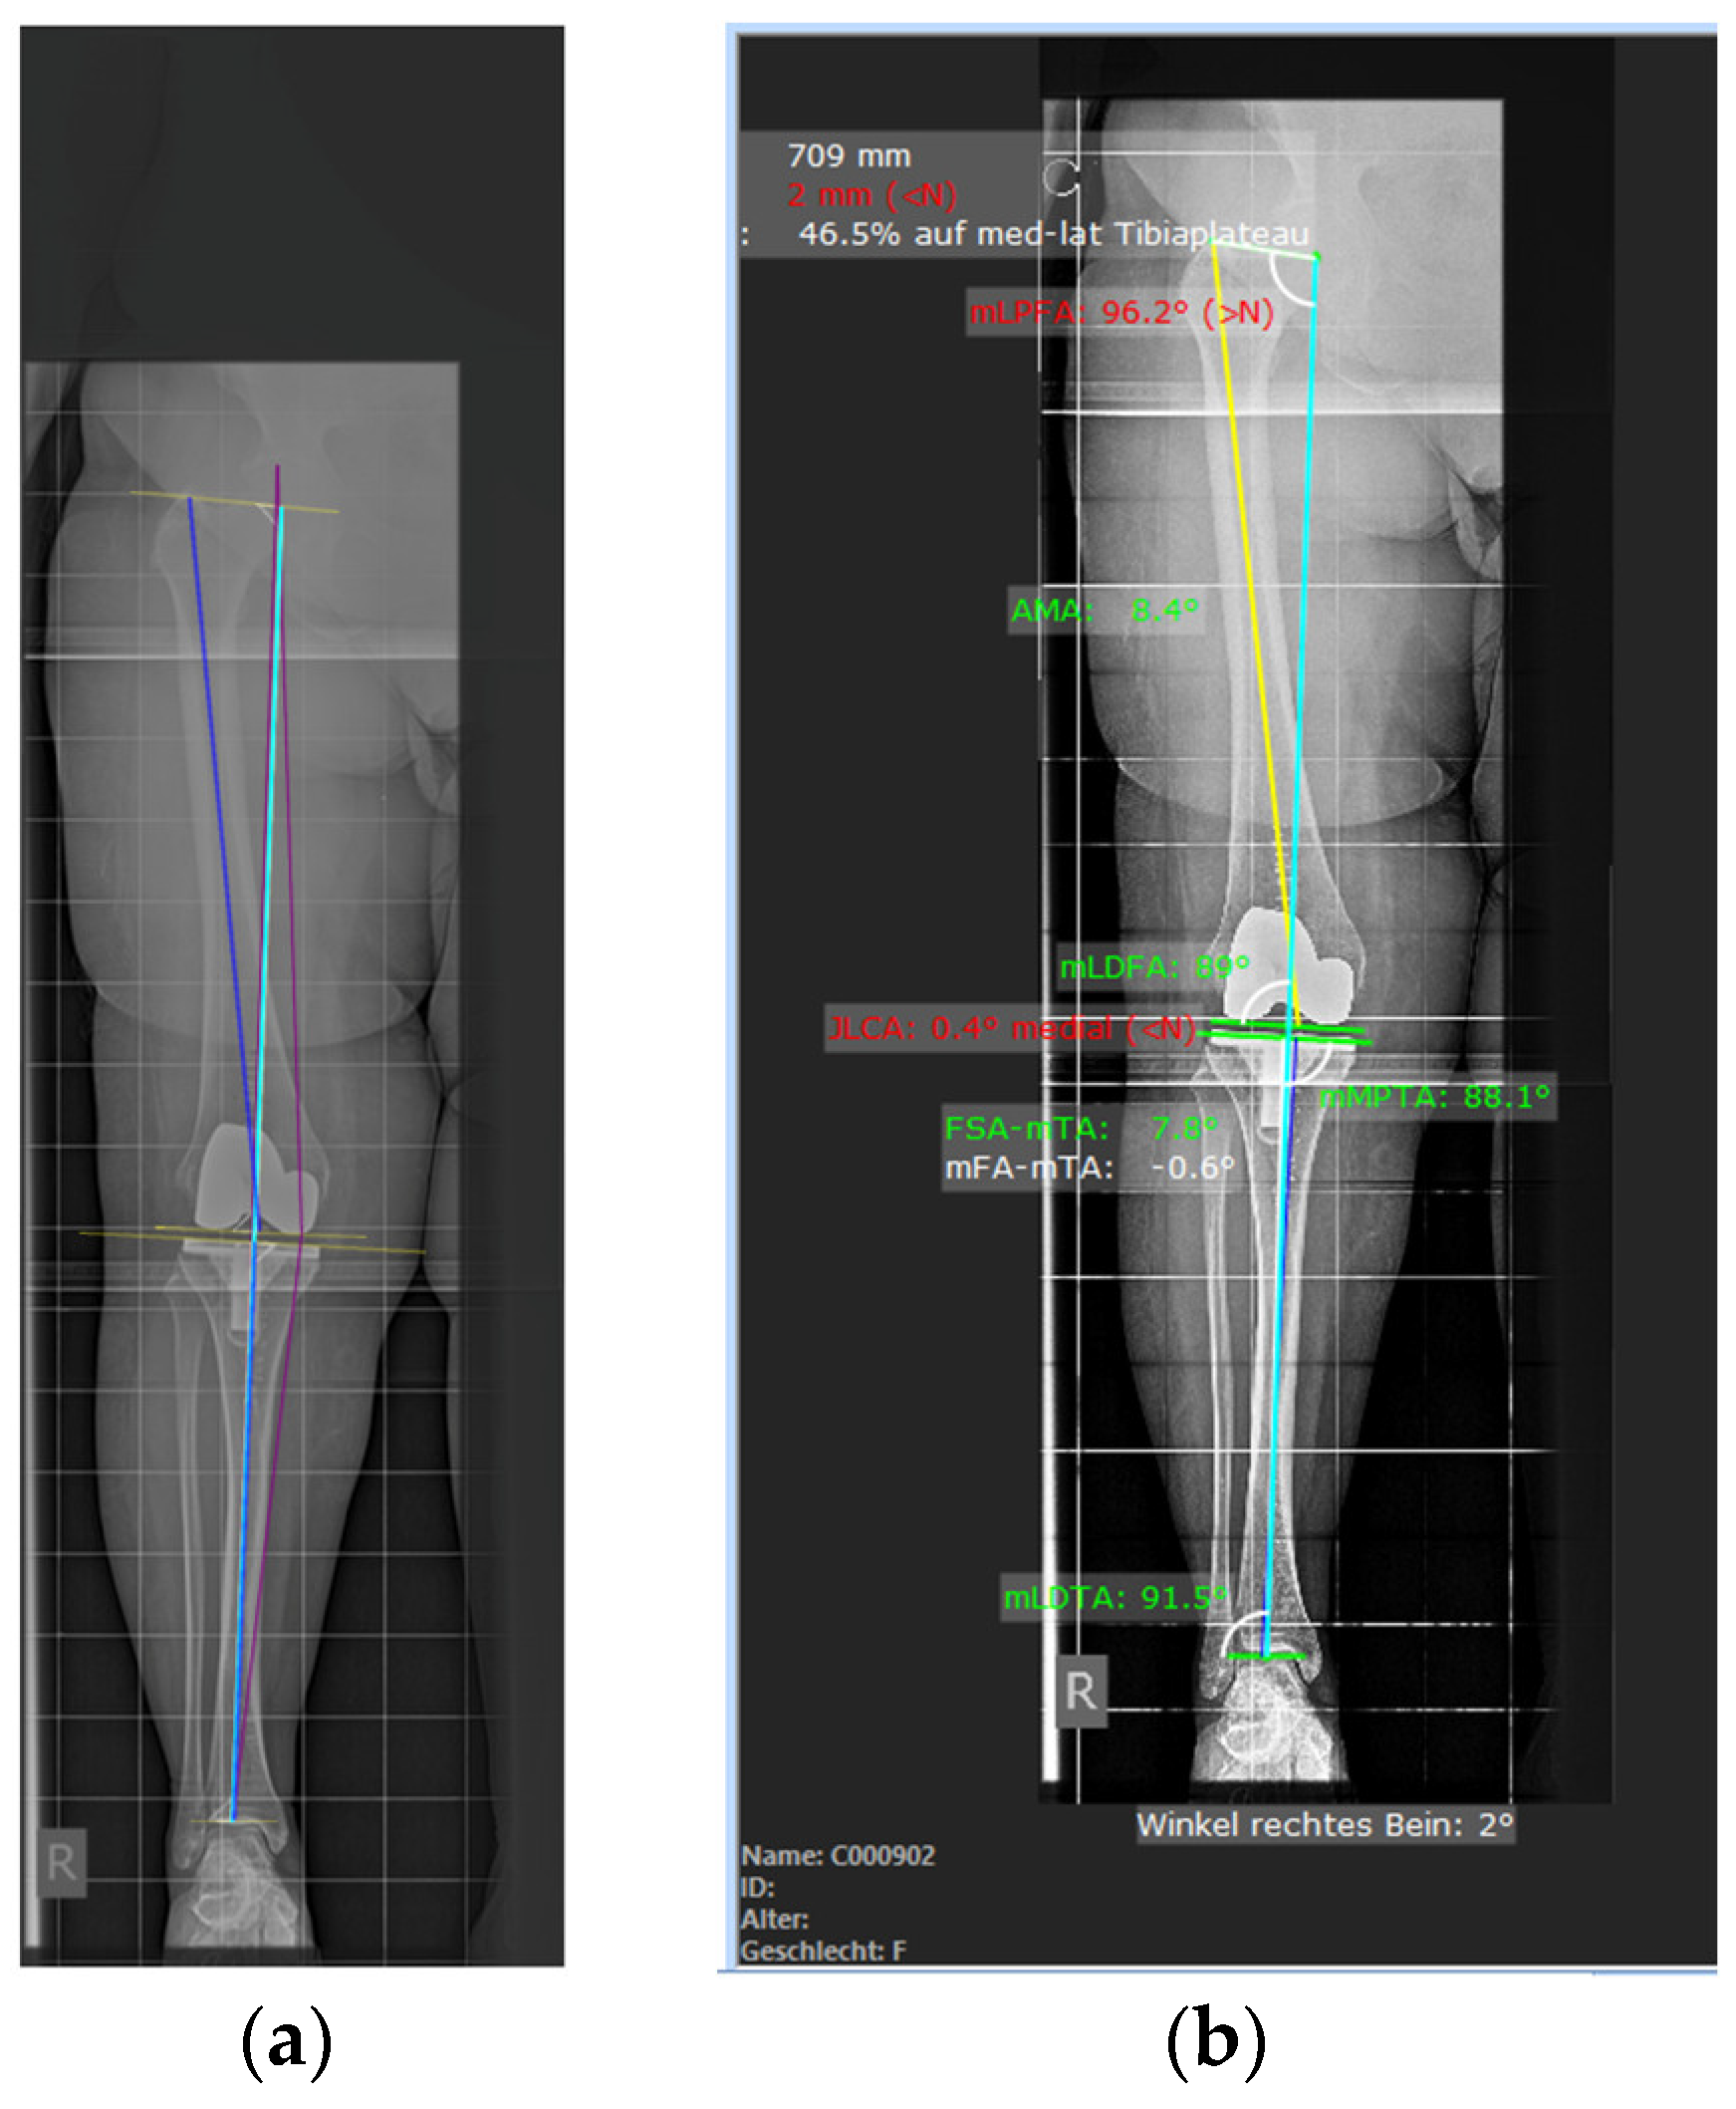

2.3. Evaluation of Radiographs